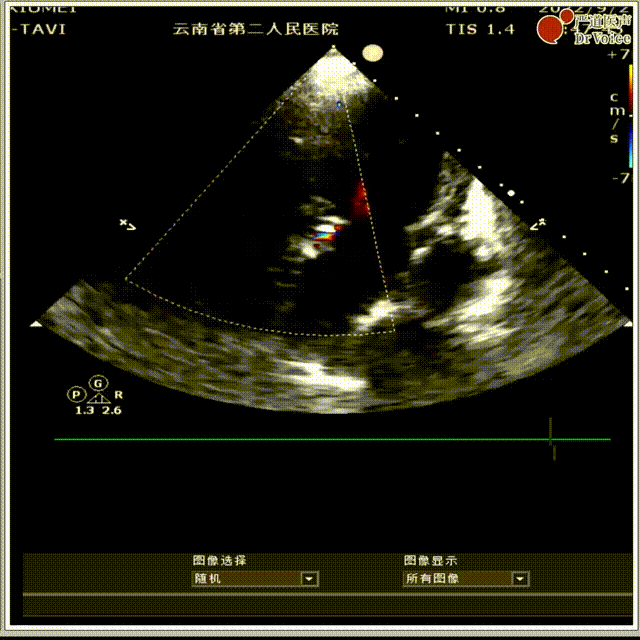

9. 术后超声评估。

最后瓣膜植入情况

术后超声